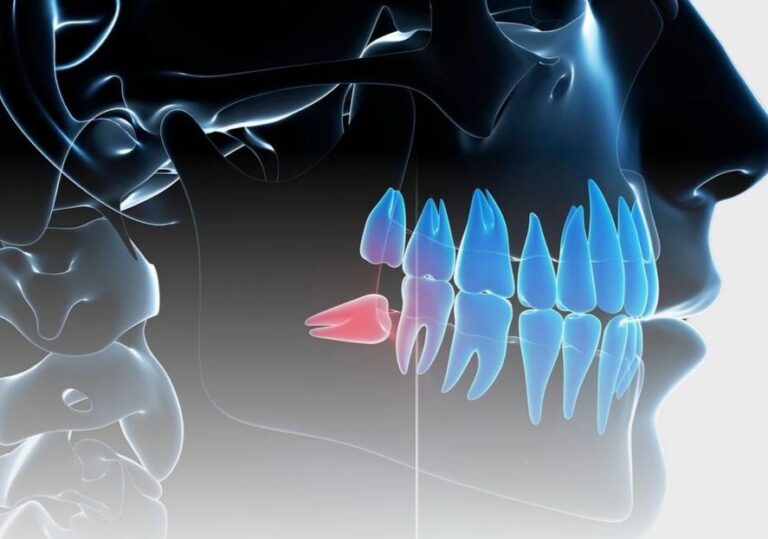

دندان عقل آخرین مجموعه از دندانهای آسیای بزرگ است که معمولاً بین سنین ۱۷ تا ۲۵ سالگی رشد میکند. ب…